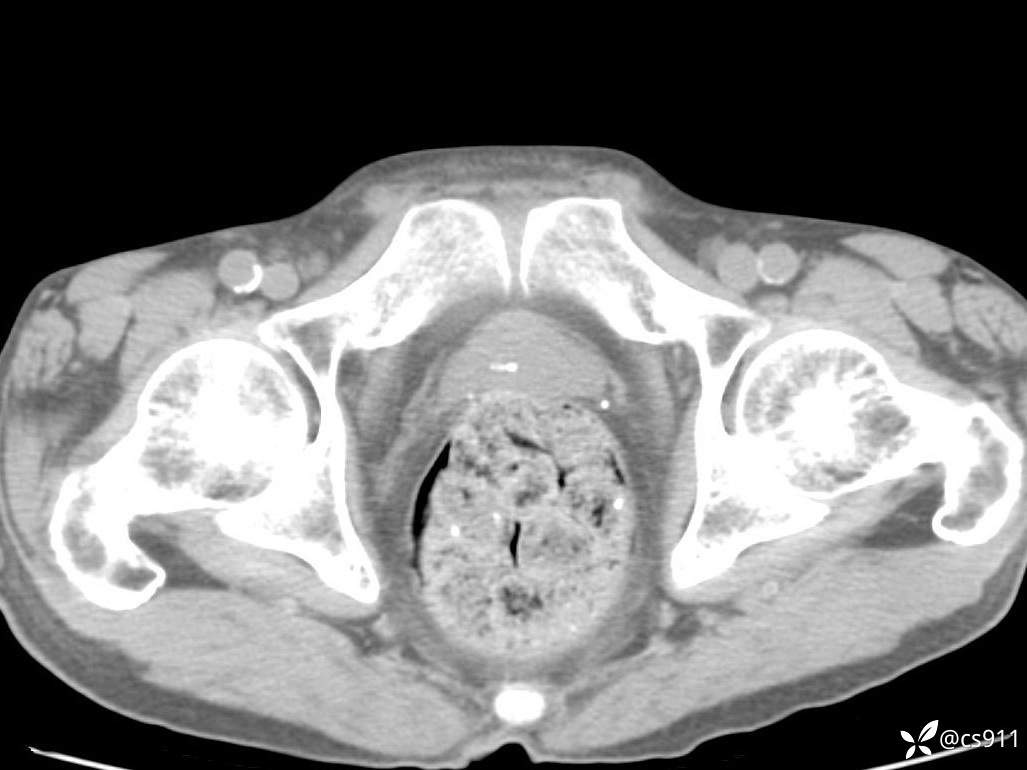

急腹症之急诊CT,原因?答案公布

男,77岁,腹痛、腹胀伴恶心呕吐1天。呕吐胃内容物,非喷射性呕吐,有咖啡色样胃内容物,诉有胃穿孔病史。查体:全腹平,下腹部压痛,全腹无反跳痛,叩诊呈浊音,移动性浊音阴性,肠鸣音减弱,1-2次/分。肛检:直肠未扪及明显肿物,可触及大量粪块。

T 36.6℃ P 80次/分 R 26次/分 BP 100/60mmHg

白细胞(WBC) H 14.55 10e9/L 4-10

红细胞(RBC) 4.58 10e12/L 4.3-5.8

中性粒细胞百分率(NEUT%) H 85.7 % 40-75

血淀粉酶(AMY) HH 1859 U/L 35-135

癌胚抗原(CEA) H 27.44 ng/ml 0-5

呕吐物 潜血试验 * 阳性 阴性

患者轮椅入室检查神志清楚, 能配合摆位和呼吸